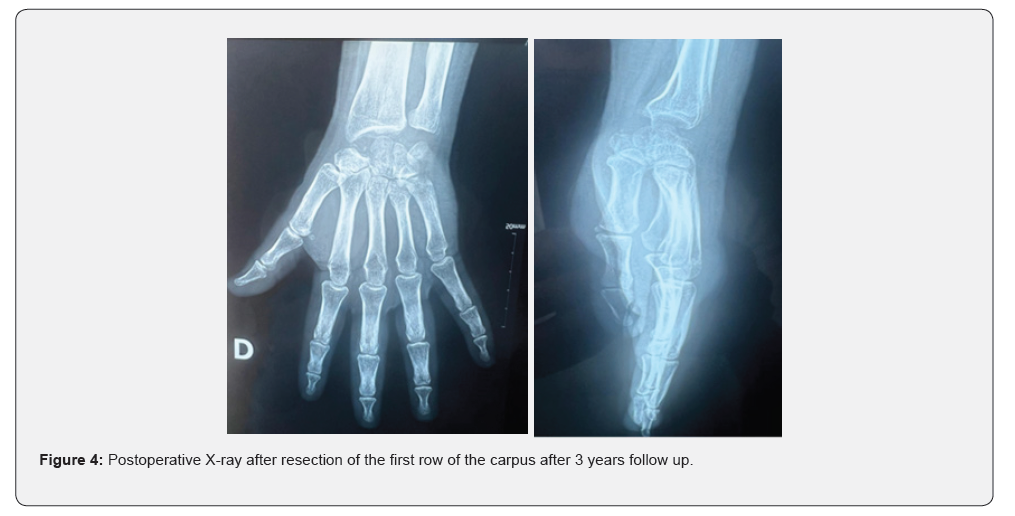

A radiological assessment consisting of a conventional wrist X-ray in both frontal and lateral views, as well as CT, was performed on all patients, allowing for classification of the patients at stage III and IV of Lichtman (Figure 1). All patients underwent the same surgical technique through a posterior approach. The procedure involved opening the retinaculum and denervation of the NIP (nervus interosseus profundus). A T-shaped arthrotomy was performed, followed by resection using a cold blade while preserving the anterior capsuloligamentous plane (Figure 2). Pain significantly decreased in all patients. The VAS score decreased from an average of 6.5 ± 1.2 before the procedure to 2.3 ± 1.1 at the last follow-up (p < 0.01). This pain reduction was consistently observed throughout the follow-up period. Range of motion (flexion/extension) also showed notable improvement. The average flexion/extension increased from 65° ± 10° preoperatively to 85° ± 8° postoperatively (p = 0.02). This improvement allowed the patients to regain satisfactory functional mobility (Figures 3 & 4). Grip strength significantly improved. It increased from 55% ± 8% of the strength of the healthy side to 72% ± 6% at the last follow-up (p = 0.03). The functional wrist score (DASH) decreased, reflecting an improvement in quality of life. The average score dropped from 32 ± 7 preoperatively to 14 ± 5 postoperatively (p < 0.01). No major complications were reported during the follow-up. One patient developed mild carpal osteoarthritis at 4 years postoperatively, but this did not require further intervention.